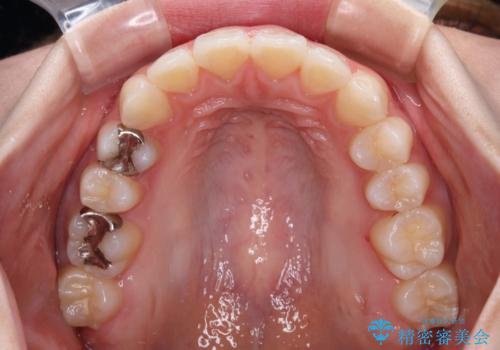

上顎歯列全体を後方移動させたことで唇に当たる感覚は改善され、更には上下の正中位置も合わせることができました。